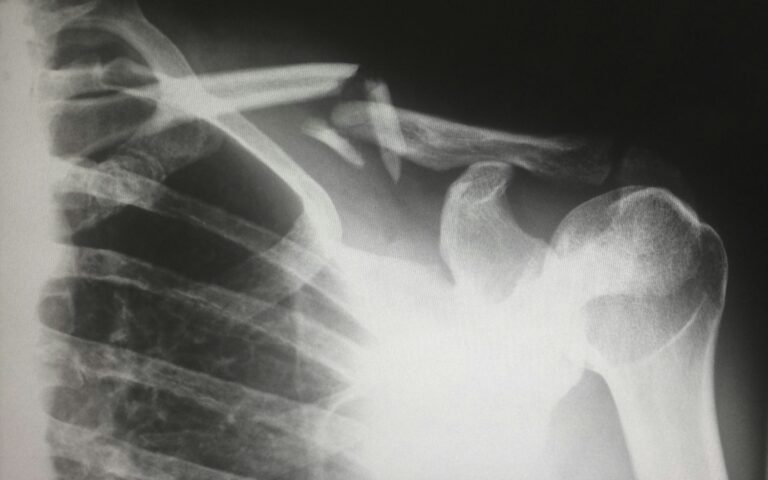

Bone fractures are often the result of extreme stress placed on a bone. There are many different types of breaks you can endure, which range in severity. For example, a comminuted break occurs when the bone shatters in the location of the fracture, while a hairline fracture is a small break in the bone that does not go all the way through. Additionally, a compound fracture occurs when the bone breaks fully in half, splitting into two independent pieces.

You should also note that bone fractures can be open or closed. Essentially, an open fracture occurs when a portion of the broken bone pierces through the skin and remains visible outside of your body, while a closed fracture remains under your skin. While all fractures are serious and painful, these also pose a greater risk of infection due to the open wound.